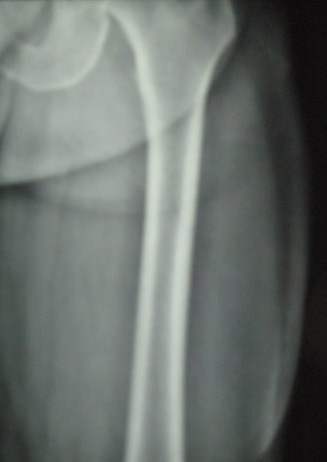

Il s'agit d'un homme âgé de 60 ans qui visite le Laos en moto. Il tombe et glisse sur la chaussée avec un impact sur sa cuisse gauche d'une manière tangentielle.

Dans les heures qui suivent apparaît une tuméfaction de la cuisse gauche. Il consulte sur place où cette tuméfaction est ponctionnée, mais rapidement la tuméfaction récidive. Il consulte à son retour à Paris 15 jours après le traumatisme. La tuméfaction est nette, rénitente, molle, indolore. L’examen est par ailleurs normal.